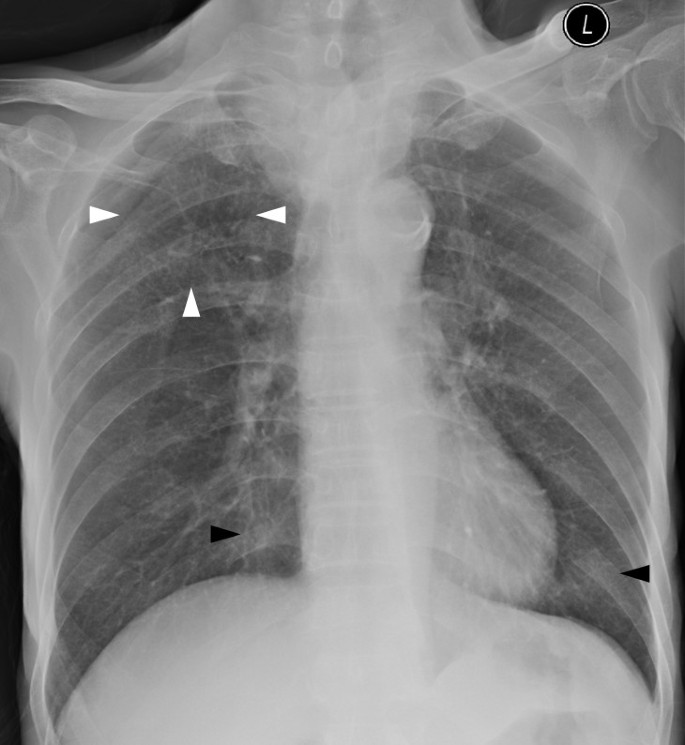

A 65-year-old man with locally advanced esophageal carcinoma and right supraclavicular nodal metastasis presented with cough, dysponea and neutropenic fever on the 5th day of the 1st of palliative chemotherapy (carboplatin). His initial CXR showed clear lungs and right supraclavicular lymphadenopathy which compressed and deviated the trachea (Figure4).

Serial chest radiographs revealed bilateral migratory air space opacities and progressive bilateral miliary nodules (Figure5). The initial ANC was low (0.55x10*9/L) and CRP level was elevated (66.6 mg/l). Initial septic workup was negative, which included sputum bacterial culture, sputum and bronchoalveolar lavage (BAL) AFB smear, culture, and polymerase chain reaction (PCR), nasopharyngeal aspirate viral titre and culture, blood culture, hepatitis serology, urine microscopy and culture. Thoracic CT demonstrated bilateral ground glass opacities and numerous centrilobular nodules. There was fistulation between the right supraclavicular nodal metastasis and the trachea. A diagnosis of chest infection was made. Chemotherapy was withheld and Piperacillin/ Tazobactam (Tazocin) was started as empirical treatment. Follow up thoracic CT during treatment demonstrated progression of bilateral ground-glass opacities and centrilobular nodules, and newly developed diffuse cylindrical bronchiectasis and bronchial wall thickening (Figure6). Repeated sputum culture demonstrated heavy growth of S. maltophilia which was sensitive to Cotrimoxazole, Levofloxacin, Ticarcillin/ Clavulanate (Timentin), intermediate to Cefepime, Cefoperazone/ Sulbactam, Ciprofloxacin, and resistant to Ceftazidime, Imipenem, Meropenem, Piperacillin/ Tazobactam (Tazocin). The antibiotic regime was switched to Ticarcillin/ Clavulanate and Levofloxacin accordingly. The patient became afebrile and weaned off oxygen supplement after completion of a course of antibiotics. His ANA normalized and CRP level dropped. Post treatment CXR showed marked regression of the lung nodules and air space opacities (Figure7), with only small amount of nodules remained at the right upper zone and minimal increase in lung markings at bilateral lower zone. Thoracic CT was not repeated. Despite successful treatment, the patient succumbed to advanced malignancy two months later.

To the best of our knowledge, there is only one case report describing the CT features of S. maltophilia[23]. In that case, multifocal areas of air-space consolidation, ground-glass attenuation areas, small centrilobular nodules and bronchial wall thickening were present. In our series, the sole CT finding of patient 1 is bilateral patchy ground glass opacities without zonal predominance. Air-space consolidation, ground glass opacities, numerous centrilobular nodules and bronchial wall thickening are noted in patient 2. These are similar to those described in prior case report. Compared with that reported case, the only new imaging finding in patient 2 is bilateral cylindrical bronchiectasis. Among all three cases, diffuse ground glass opacities without zonal predominance is the most consistent CT features of S. maltophilia pneumonia. Other imaging findings such as bilateral multifocal areas of air-space consolidation and centrilobular nodules can be occasionally found. Bronchiectasis likely represents the later stage of pneumonia. However, since these imaging features and pattern are not specific nor diagnostic, the final diagnosis of S. maltophilia pneumonia still relies on microbiology results.

Stenotrophomonas maltophilia is a rare yet important globally emerging opportunistic pathogen. The most consistent CT features of S. maltophilia pneumonia is diffuse ground glass opacities without zonal predominance. Bilateral multifocal areas of air-space consolidation, centrilobular nodules, bronchiectasis and bronchial wall thickening are occasionally found. Due to its supreme sensitivity, the role of thoracic CT in the detection and exclusion of pulmonary infection, including S. maltophilia pneumonia, in neutropenic febrile patients cannot be overstressed.